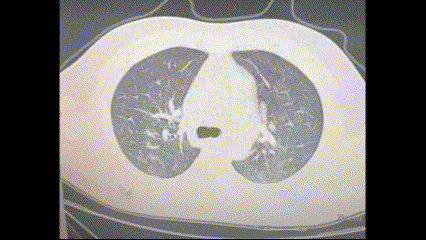

Các cụm màu trắng xuất hiện trên hình chụp cắt lớp vi tính (CT) và chụp X-quang là những dấu hiệu của chứng viêm phổi, cả hai đều là những dấu hiệu đáng lo ngại thường thấy ở các bệnh nhân COVID-19 từ trung bình đến nặng.

Tình trạng trắng xóa trong ảnh chụp cắt lớp vi tính (CT) là một dấu hiệu cho thấy bệnh đã đến mức nặng. “Phổi càng trắng, thì người ta càng có nhiều khả năng tử vong,” ông Varon nói, đề cập đến một nghiên cứu về tiên lượng bệnh mà ông là đồng tác giả.